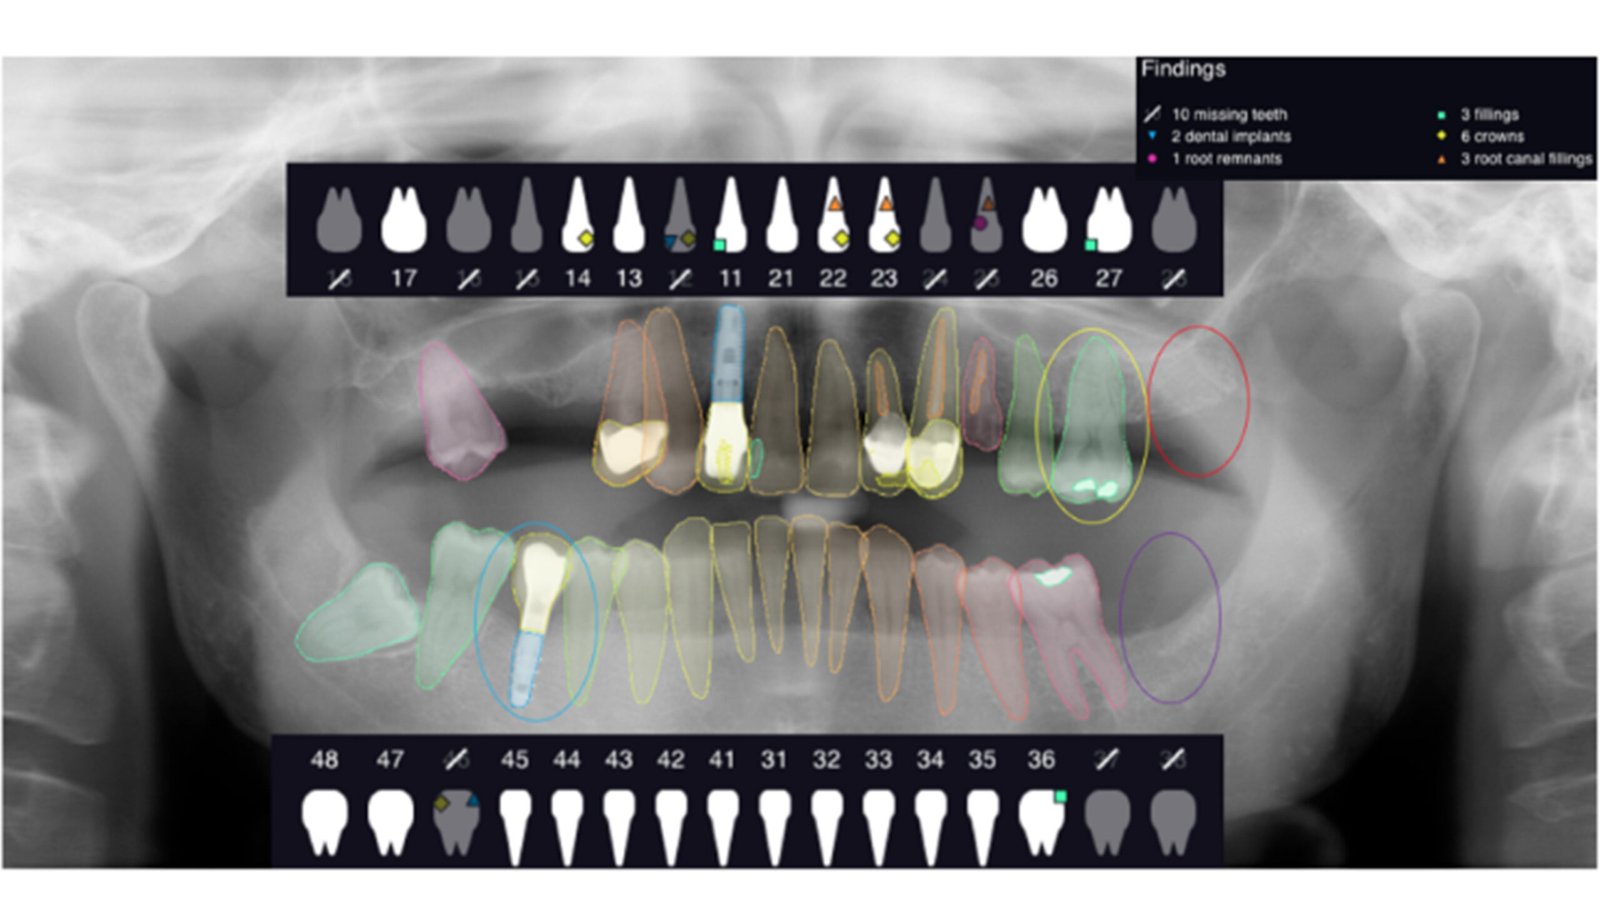

Leveraging AI-driven simulations, this segment integrates predictive modeling with clinical design. We optimize prosthetic, implant, and restorative solutions by forecasting mechanical performance, identifying risk areas, and supporting data-driven treatment planning.